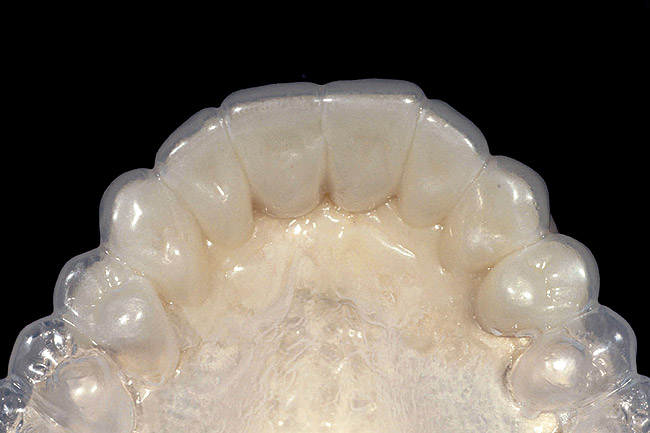

Figure 17  A 1.5-mm clear matrix is tried on a model of the preparations prior to indirect temporary fabrication.

Figure 17

To reinforce temporary restorations, begin by preparing the teeth and making an impression of the preparations. Pour the impression with one-third die stone and two-thirds mounting stone, so it sets quickly. Then ensure that the matrix fits the model. The fiber can now be placed across the preparations on the model and tacked into place with flowable composite. Once the fiber is positioned, try the matrix back on to verify clearance between the fiber and the matrix. If the clearance is acceptable, remove the matrix and reinforce the fiber by adding more flowable composite across its length. Finally, lubricate all areas of the model with petroleum jelly or foil substitute, keeping all lubricant off the fiber. Then, load the matrix with the desired temporary material and seat it over the preparations and the fiber. After curing, it can be trimmed and seated in the patient’s mouth (Figure 17, Figure 18, Figure 19, Figure 20 and Figure 21).